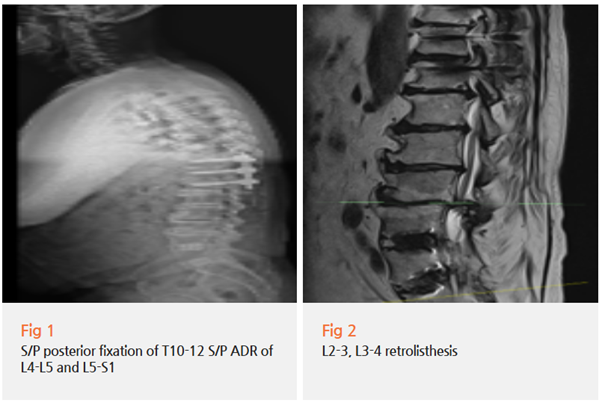

지난달 처음 오신 75세 환자분 한 분이 계셨어요.

허리 인공디스크 수술 한 번, 등쪽 척추 유합술 한 번.

총 두 번의 수술을 받으신 분이었습니다.

당일 MRI를 찍어보니 수술 부위 자체는 큰 문제가 없었어요.

그런데 문제는 다른 곳에 있었습니다.

✅ 수술 주변 근육이 많이 약해져 있었고

✅ 인접한 다른 부위에서 신경이 눌리고 있었어요

✅ 만성 염증이 계속 신경을 자극하고 있었습니다